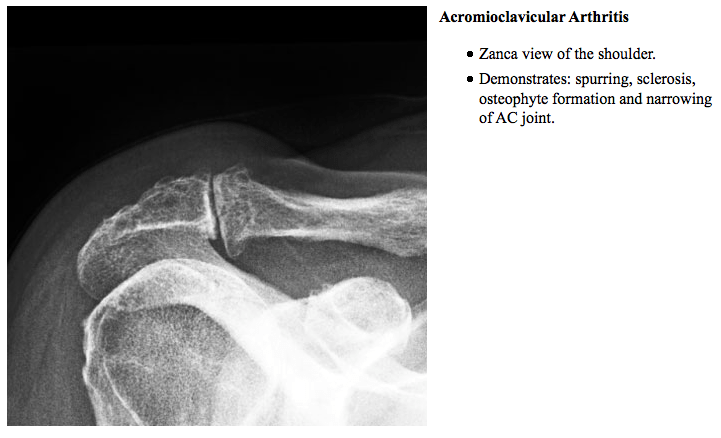

Ac Joint Separation Radiology

In a cadaveric study, acromioclavicular joint injection without imaging guidance was technically successful (purely intraarticular) in only 67% (16/24 joints). Ac joint separation usually results from a force applied downward on the acromion. 12% of shoulder dislocations involve ac joint.

Ac joint space is usually <5mm. The most common etiologies of pain are posttraumatic. Use a focused physical exam and imaging to make the diagnosis.

Acromioclavicular (ac) joint pathology can be divided into conditions that cause pain or conditions of instability that may cause pain or compromise function. For this reason, we use. The acromioclavicular joint is an important component of the shoulder girdle;

The clavicle rests against the first rib, and the rib blocks further downward displacement of the clavicle. The acromioclavicular joint is a common source of “shoulder pain” aside from the glenohumeral joint and rotator cuff. Football players and cyclists who fall over the handlebars are often subject.